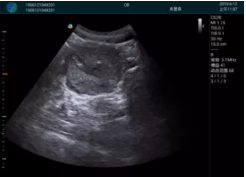

M20實時引導:向包塊后方間隙注射利多卡因

清晰顯示腺體內低回聲快影,邊界清晰,包膜較光滑

確定進針路徑并實時監(jiān)測抽吸針與腫塊位置關系

抽吸針進入腫塊內部進行旋切

抽吸過程中可見腫塊明顯縮小,并根據腫塊位置改變針道位置

抽吸旋切后再進行超聲復查,原腫塊區(qū)域未見殘留組織及出血

超聲引導下抽吸旋切取出的腫塊組織